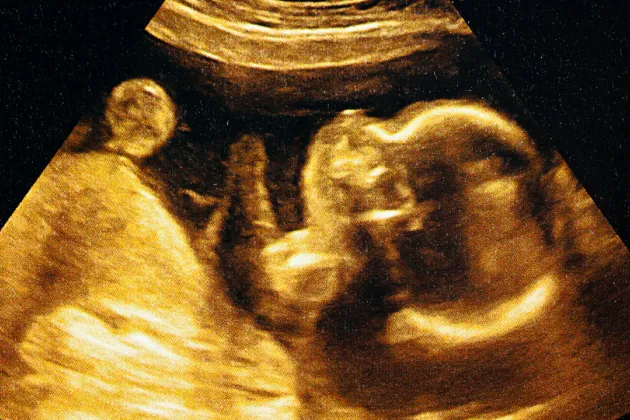

Therefore, we hypothesized that there may be a protein that acts as a tumor inhibitor during these early stages of life, preventing the development of leukemia. We explored different aspects of this throughout the four papers detailed in my kappa – one of which was published earlier this spring and another which we are planning to submit soon. Since these mutations occur in utero and are very hard to study in humans, we used mouse models that express the same genetic mutations to investigate their impact on the blood or hematopoietic system.

As opposed to MLL fusion leukemia, ETV6-RUNX1 (E/R) leukemia is a less aggressive but more prevalent type of leukemia in older children. The first mutation also occurs in utero, but more mutations are needed to develop E/R leukemia. It can take over 15 years from when the first mutation occurs to when the second mutation occurs. Although, the incidence of E/R leukemia in adults is low.